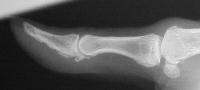

Plain films showed resorption of the distal two thirds of the distal phalanx:

Click for larger image